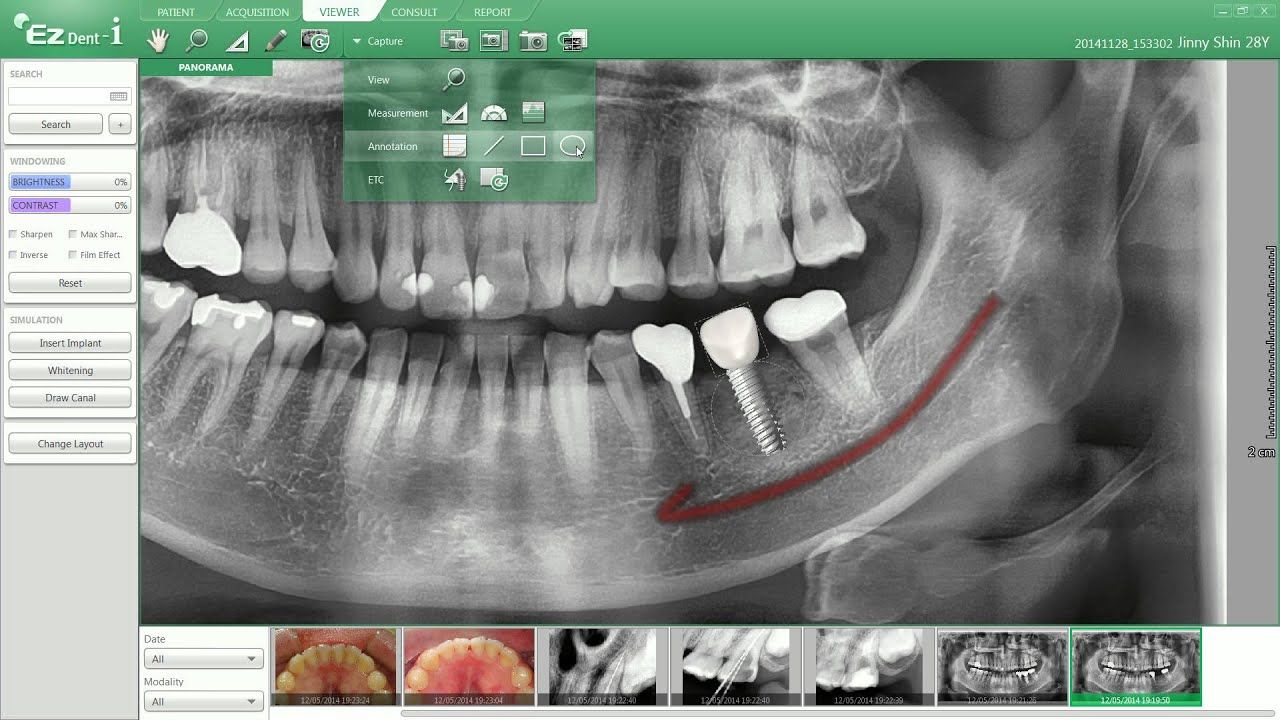

Tac dental 3D o CBCT.

TAC de cráneo (Cone Beam)

Mi dentista me derivó para hacerme un TAC y encontré esta clínica por internet. La experiencia fue excelente. El proceso de cita fue rápido y sencillo a través de Doctoralia, y en la clínica fueron muy puntuales. El personal fue amable y me explicaron todo antes de realizar la prueba. La máquina era moderna y el procedimiento fue rápido y cómodo. Me enviaron las imágenes en el formato que necesitaba sin ningún problema. Muy recomendable si necesitas un TAC dental.”

• Clínica Dental Dr. Iván García • TAC de cráneo (Cone Beam) •